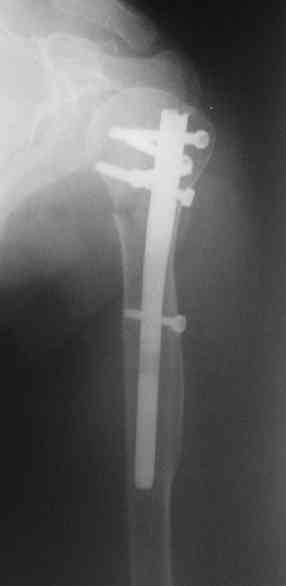

Another option could be closed nailing, see an example, the surgery was

done 2 days ago. In common such surgeries are performed under regional

anesthesia, not general.